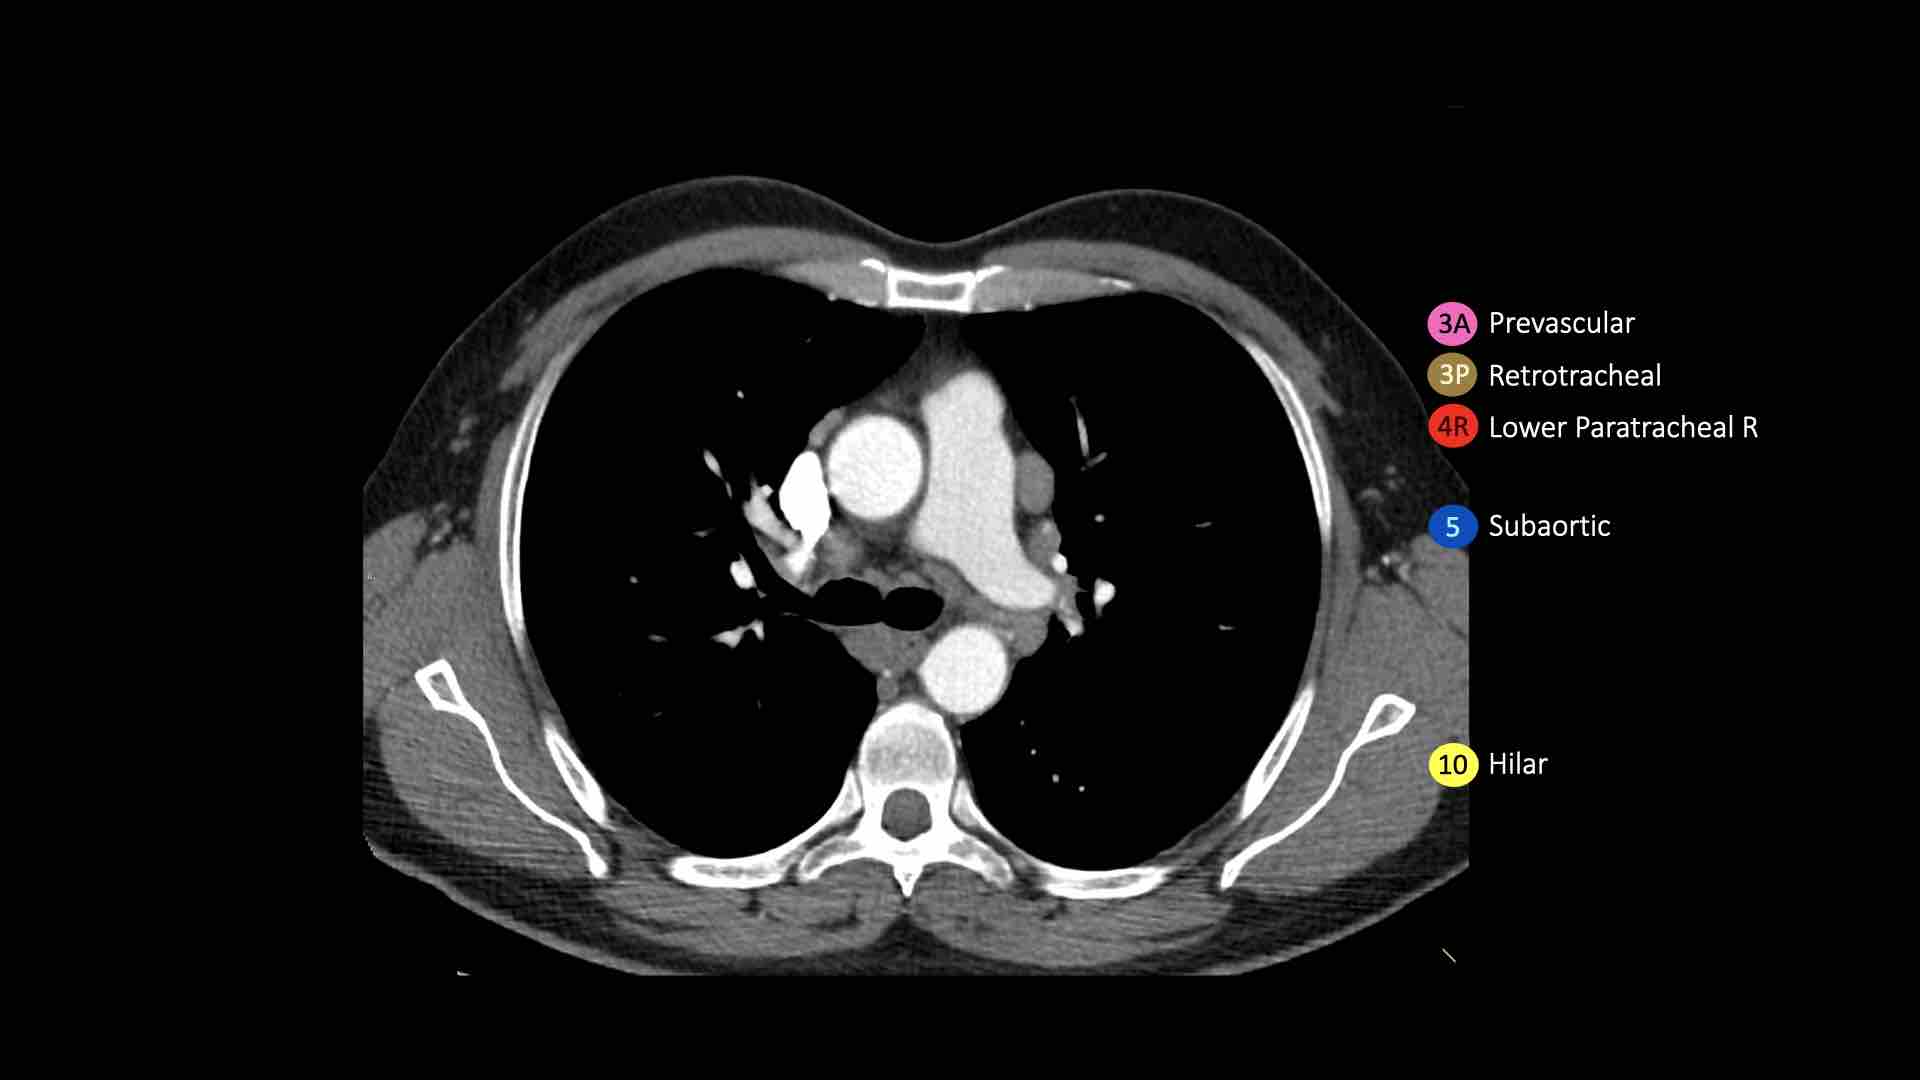

5. Hạch dưới động mạch chủ

Hạch dưới động mạch chủ hay hạch cửa sổ phế động mạch nằm ở phía ngoài dây chằng động mạch hoặc động mạch chủ hoặc động mạch phổi trái, ở đoạn gần trước nhánh đầu tiên của động mạch phổi trái, và nằm trong bao màng phổi trung thất.

10. Hạch rốn phổi

Bao gồm các hạch tiếp giáp với phế quản gốc và các mạch máu rốn phổi.

Bên phải, trải dài từ bờ dưới tĩnh mạch đơn đến vùng gian thùy.

Bên trái, từ bờ trên động mạch phổi đến vùng gian thùy.

Hạch rốn phổi là các hạch thùy gần, nằm ở phía xa so với nếp gấp màng phổi trung thất và các hạch kề phế quản trung gian bên phải.

Các hạch từ nhóm 10 đến 14 đều là hạch N1, vì chúng không nằm trong trung thất.